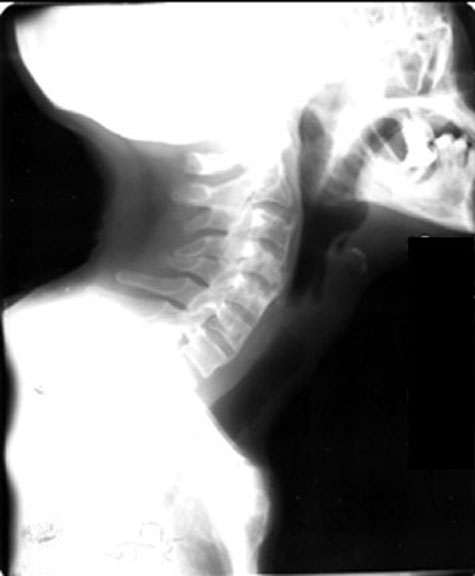

Spine

Neck

Labeled Image What are the pulmonary manifestations of Ankylosing spondylitis?